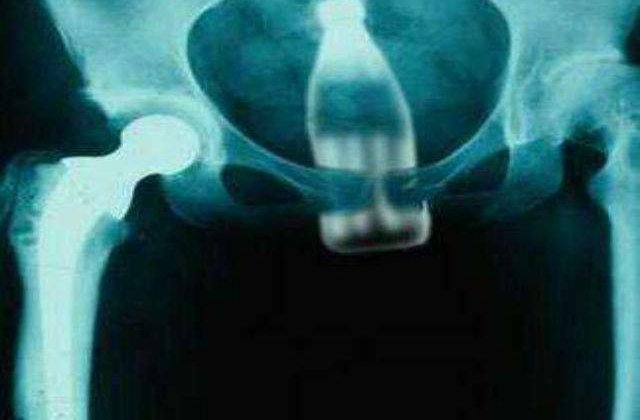

Introduse intentionat din diverse motive in corp sau doar accidental obiectele prezentate mai jos au lasat doctorii cu gurile cascate la fiecare interventie.